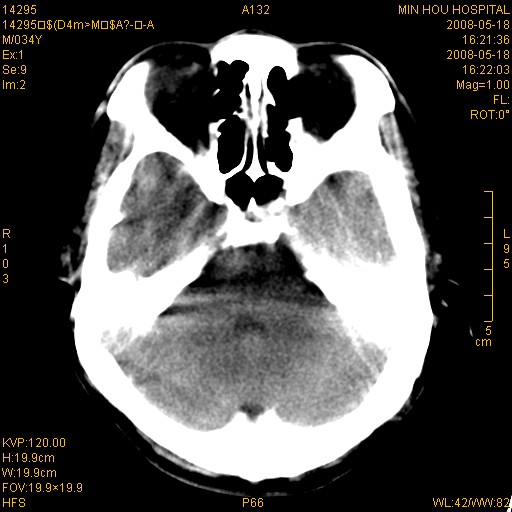

标题: CT13617:双顶叶白质水肿伴大脑镰小脑幕广泛钙化 [打印本页]

标题: CT13617:双顶叶白质水肿伴大脑镰小脑幕广泛钙化

多年前频发抽搐生活不能自理,行ct平扫,诊断为双顶叶占位。因贫未能进一步检查。

目前偶有抽搐,能从事油漆工作。原片未能获取。

双侧侧脑室后脚旁对称性低密度影,符合肾上腺白质营养不良(成人型)改变    小脑幕及大脑廉钙化  可考虑为生理性

支持:1、肾上腺白质营养不良.2、小脑幕、大脑镰广泛钙化。3、建议进一步检查。

硬脑膜钙化是主因,双侧顶叶白质密度减低是可能由于静脉路回流受阻所致。